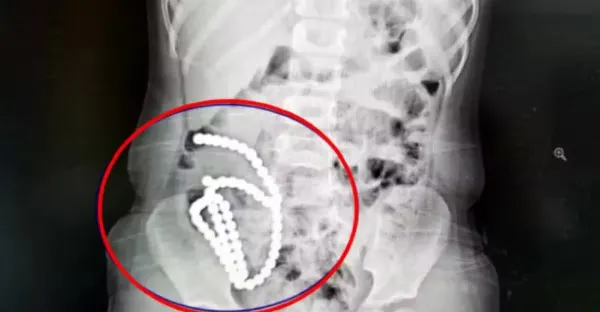

4歲妹照X光驚見「肚子整串白珠珠」 媽證實哥哥在玩!醫嘆:一輩子毀了.